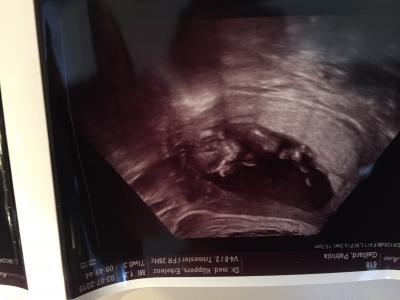

Der Ultraschall gestern war sehr schön. Meine zwei Kleinen waren mit und total begeistert von dem zappelnden Baby. Und es wird wahrscheinlich ein kleiner Junge. Bei den zwei Großen hat er auch relativ früh das Geschlecht erkannt, von daher vertrau ich ihm auch diesmal.

Bild zu großer Ultraschall & vorsichtiges Outing - Forum für Januar - Mamis